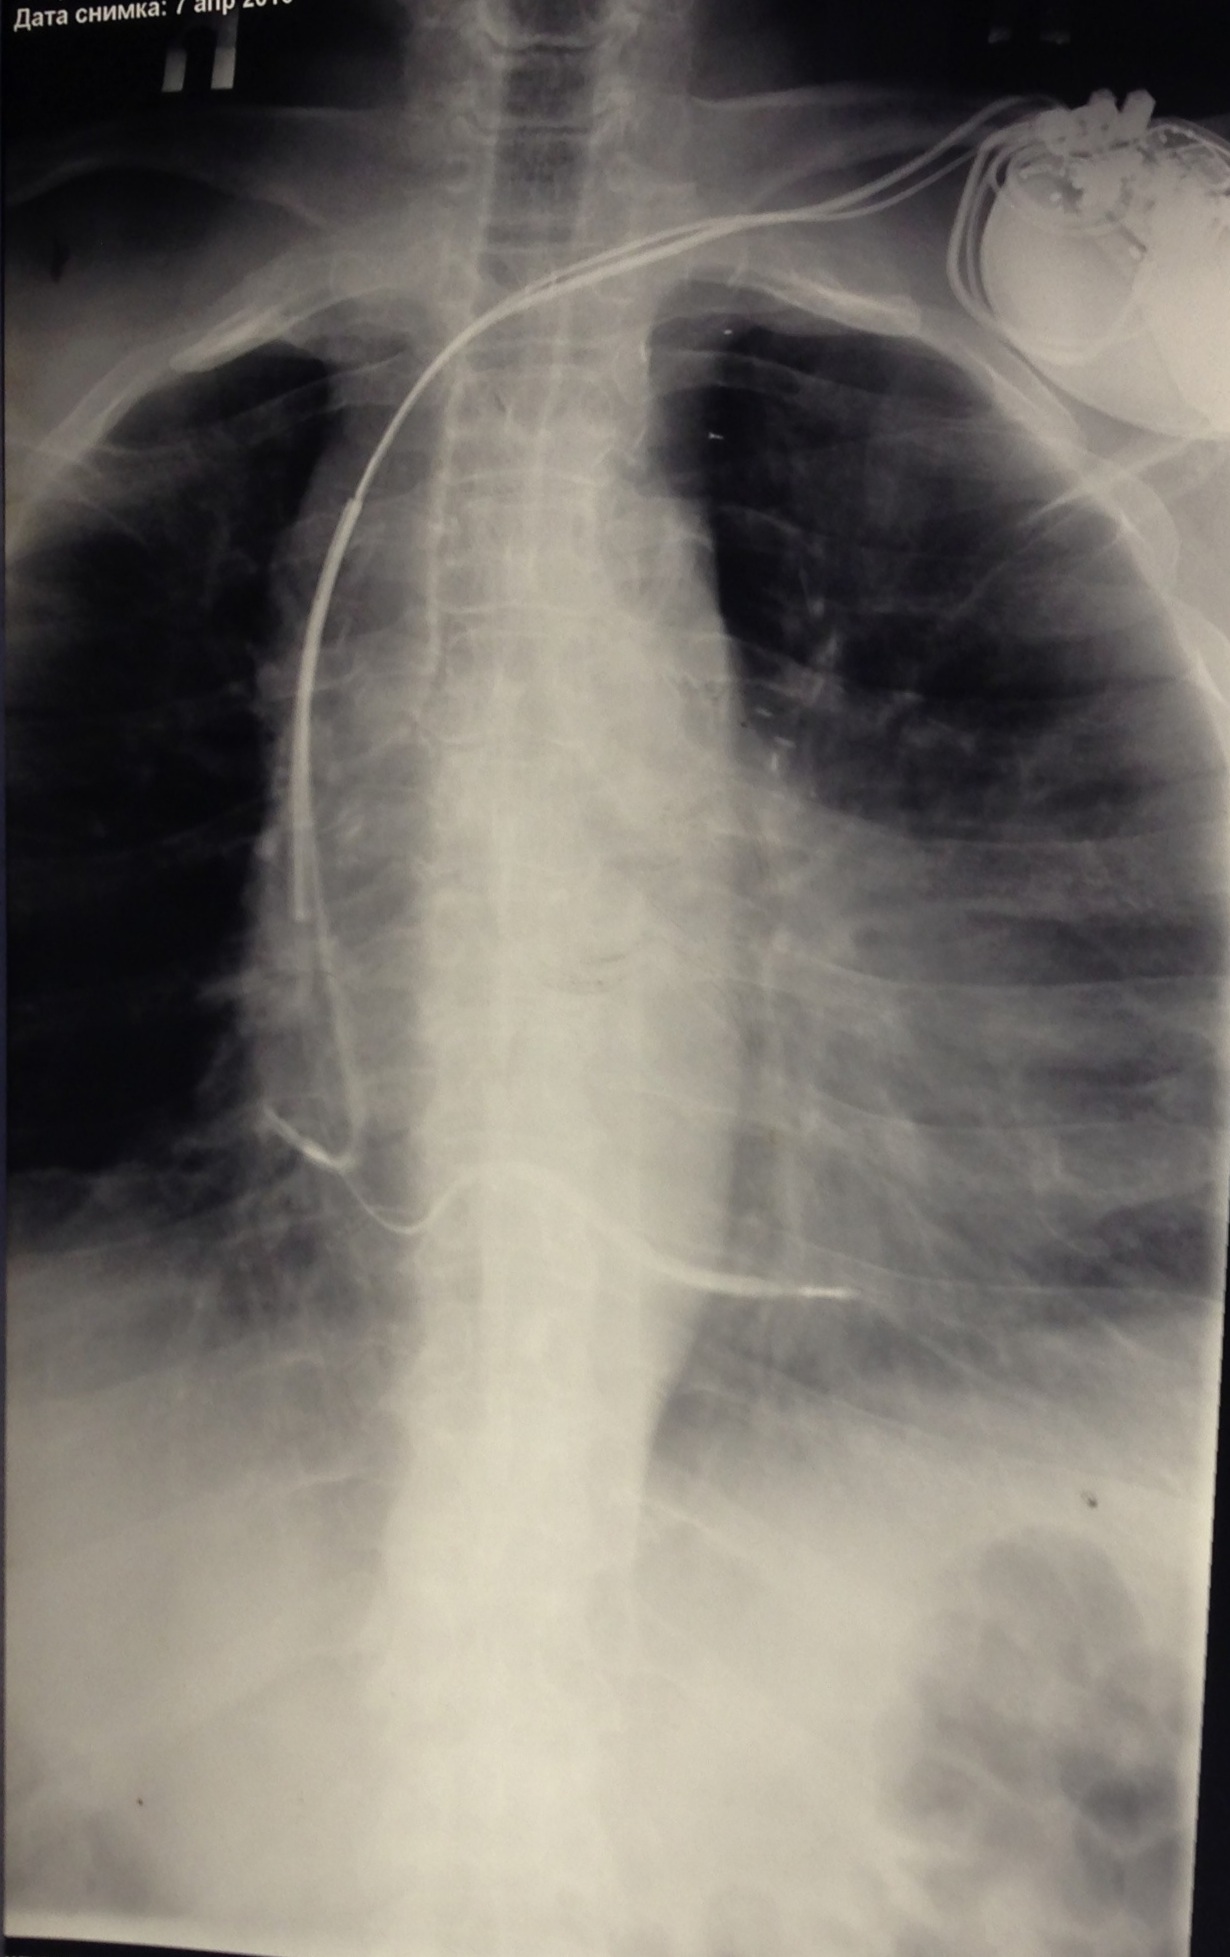

ИКД + ЭКС DDD. Когда всё на месте и всё работает.

DDD+ ICD. Все на месте